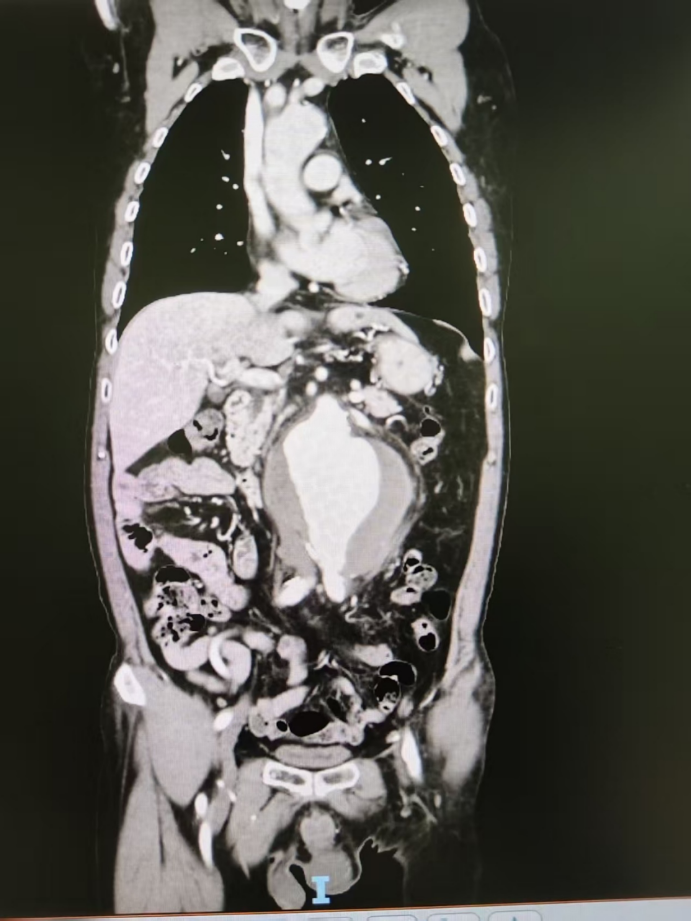

△胸腹动脉CTA。

这个瘤体非常危险——长度达12厘米,最宽处直径约10.5厘米,而他正常的血管仅有2.5厘米。就像一段水管被撑成了气球,瘤壁菲薄,随时可能破裂大出血,直接危及生命。